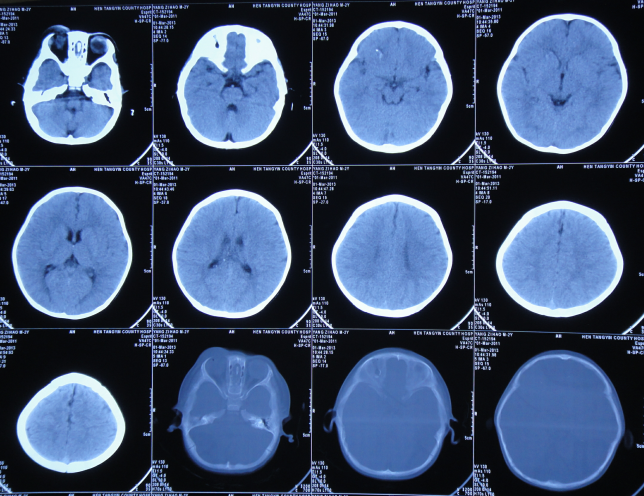

脑水肿脑积水的分类及影像表现一文归纳

成人正常脑ct和脑积水ct影像对比脑积水是由于颅脑疾患使得脑脊液分泌